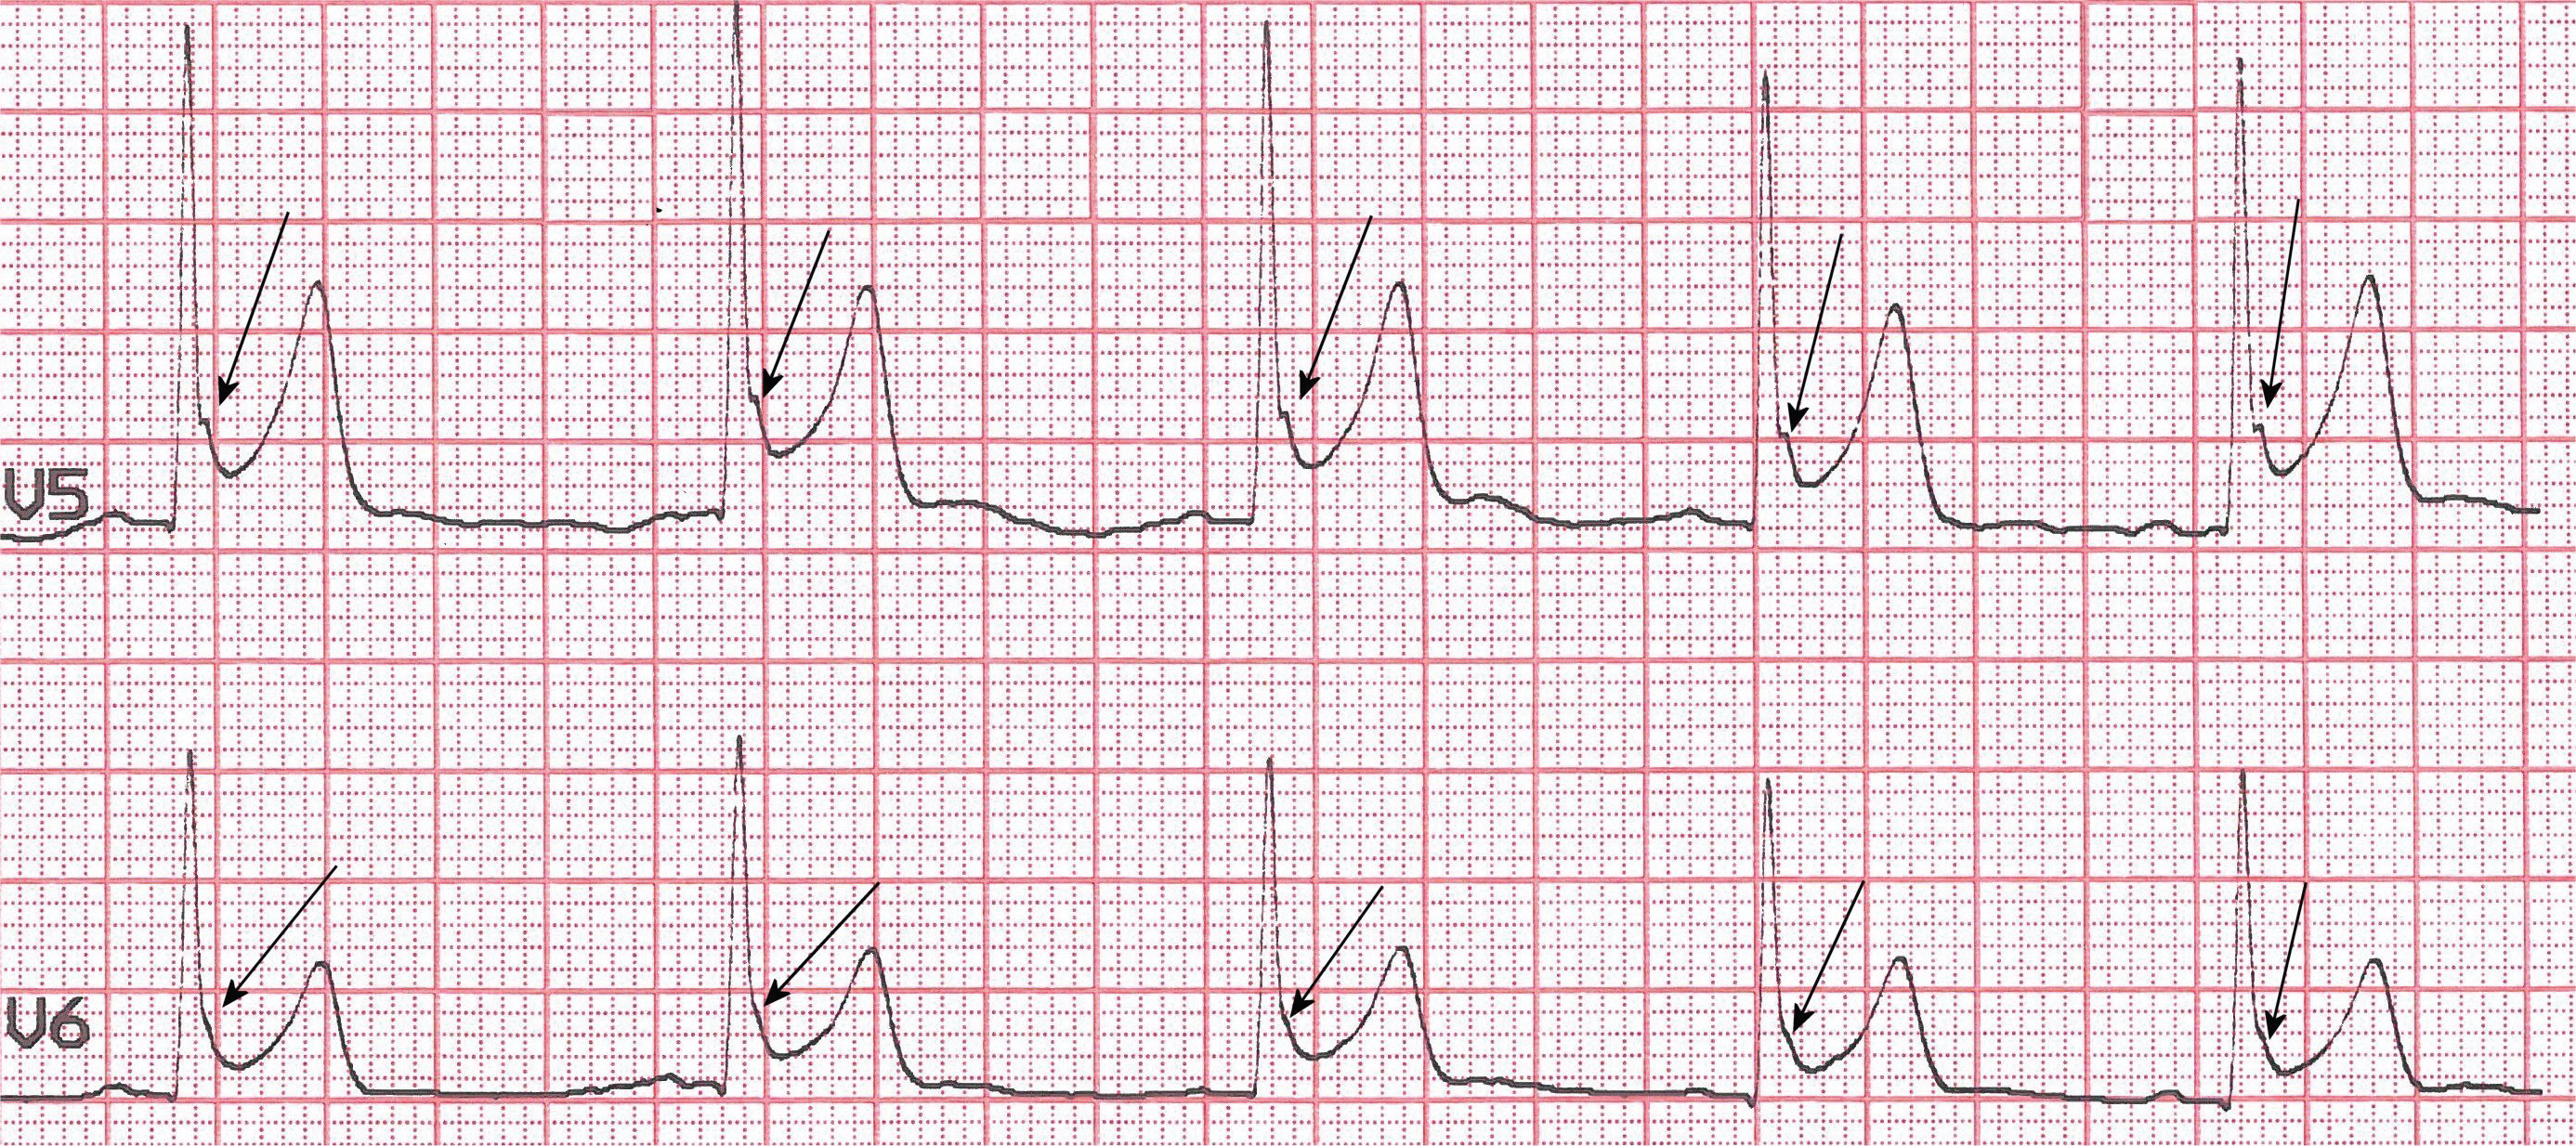

A 21-year-old, white, professional marathon runner underwent cardiovascular assessment as a part of routine screening. He had no family history of cardiac disease or sudden cardiac deaths (SCD), and no abnormalities during a physical examination were found. Laboratory studies demonstrated normal levels of electrolytes, complete blood counts and negative cardiac necrosis markers. The transthoracic echocardiography was normal. A resting 12-leads electrocardiogram (ECG) demonstrated sinus rhythm with a rate of 62 beats per minute, a moderate concave ST-segment elevation in leads I, II, aVL, aVF and more marked ST-elevation in leads V4-to V6 without reciprocal ST depression. The T waves were prominent, slightly asymmetric and concordant with the QRS complexes (Figure 1). A magnified view of lead V4 clearly showed J-point elevation with a peak of 0.2 mV and notch morphology (Figure 2 arrows), progressing to J-point elevation with a both notch and slur configuration in lead V5 to only slur morphology in lead V6 (Figure 3, arrows). This ECG finding strongly suggests an early repolarization pattern (ERP). Given the fact, that the subject was without any family history of SCD or any evidence of structural heart disease on the echocardiogram and benign ERP on ECG, he was allowed to continue with training and competition.

Figure 3: A magnified view of lead V5-V6 revealed J-point elevation with both notch and slur morphology in lead V5, progressing to only slur configuration in lead V6 (arrows). View Figure 3

The J junction is the point at which the QRS complex ends and the ST-segment begins. The J point assessment depends on its deviation from the isoelectric line (elevated or depressed) which determines the presence of J-deflection (wave), and on its shape (notched or slurred). We have presented a classic example of ERP, with a notch at the J-point in V4 (Figure 2), progressing to J-point elevation with both a notch and slur morphology in V5 to only slur configuration in lead V6 (Figure 3). The elevated ST- segment is concave, the QRS complexes durations are narrow in the leads not containing notching or slur, and the T waves are relatively tall. Actually ERP is recognized in J-point notch or slur and this is often referred to as end QRS notch or end QRS slur. Consistent with the consensus report [1] an early repolarization (ER) is present if all of the following criteria are met: 1) There is an end QRS notch (J wave) or slur on the downslope of a prominent R wave, with or without ST-elevation; 2) J peak is ≥ 0.1 mV in 2 or more contiguous leads of the 12-leads ECG, excluding leads V1-V3; 3) QRS duration is & 120 ms (measured in leads in which a notch or slur is absent). Leads V1 to V3 have been excluded from the definition of ER to avoid confusion with the Brugada pattern.